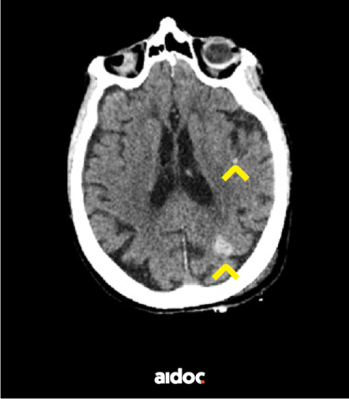

Kuva 1: Konenäkö on tunnistanut ja merkinnyt kaksi tiivistymää potilaan aivokudoksessa

Lisäksi on saatavilla ratkaisuja, jotka pystyvät laajemmin analysoimaan tietyn anatomisen alueen kuvadataa ja tunnistamaan poikkeavuudet määrittelemättä täsmälleen mistä poikkeavuudesta on kyse. Esimerkiksi aivokudoksesta tällaiset analyysit voivat tunnistaa tiivistymiä, jotka voivat johtua verenvuodosta, tulehduksesta tai kasvaimesta.

Aivokudoksesta tiivistymiä etsivän analyysin tuloksia voidaan puolestaan hyödyntää muun muassa tehtävien priorisoinnissa. Jos analyysin tulos viittaa esimerkiksi pikaista hoitoa vaativaan aivoverenkiertohäiriöön, voidaan kyseisen tutkimuksen tulkinta määritellä erittäin kiireelliseksi tehtäväksi radiologille ja lähettää hälytys päivystysyksikön hoitotiimille. Potilas saa tarvitsemansa hoidon mahdollisesti aikaisemmin kuin ilman koneen tekemää analyysia. Parhaassa tapauksessa vältytään potilaan halvaantumiselta tai jopa kuolemalta.